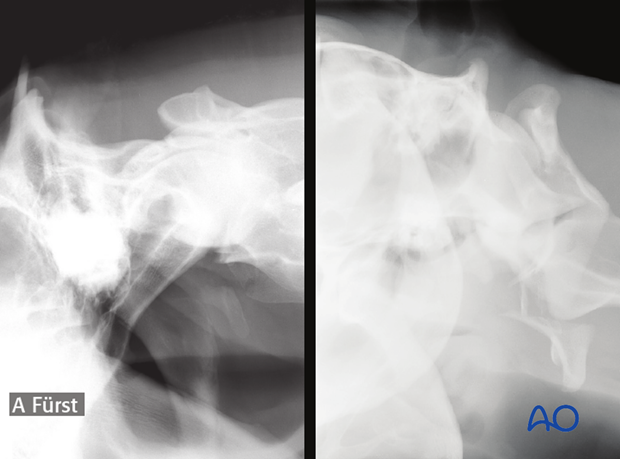

Fracture of the ventral arch of the atlas and disruption of the ligaments that secure the dens within the atlas, can lead to the formation of a bony callus that impinges on the vertebral canal and may eventually lead to ataxia.

After exposing the dorsal surfaces of the atlas, the unstable fragment or bony callus that impinges on the vertebral canal is carefully removed. The dorsal laminectomy can relieve spinal cord compression created by the fragment or fracture callus and may result in a long-term improvement in the neurologic status of the horse.